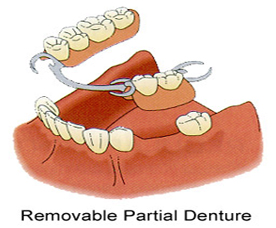

A removable denture

A removable partial denture is a set of false or replacement teeth. Dentures are either manufactured in a complete set or a partial set, depending on the amount of teeth that need to be replaced. If all of the teeth in a person’s mouth need replacement, a set of complete dentures is required. If a person has some original teeth that do not need replacement, a partial set of dentures is created to fit around the existing teeth.

Removable partial dentures may be attached to the teeth in several different ways, depending on the specific requirements of the wearer. The first type is often known as a temporary or treatment partial denture. A temporary removable partial denture typically consists off prosthetic teeth attached to a plastic or acrylic base. The denture may be attached to the teeth with metal clamps or the base may be designed and shaped to hold the denture in place. They are often used as a temporary means of preserving the oral appearance of the wearer while a longer lasting denture alternative is being manufactured.

A second type of removable partial denture is constructed around a cast metal framework and is often called a cast metal removable partial denture. These types of dentures are designed to be longer-lasting and more comfortable for the wearer than a flipper design. The teeth are attached to a gum-colored acrylic base and are connected through a metal framework that is specifically molded to fit each patient.

Most cast metal removable partial dentures are designed so that the framework does not come into much contact with the gums. This prevents oral sore spots from chafing and rubbing that is commonplace with the temporary partial denture.